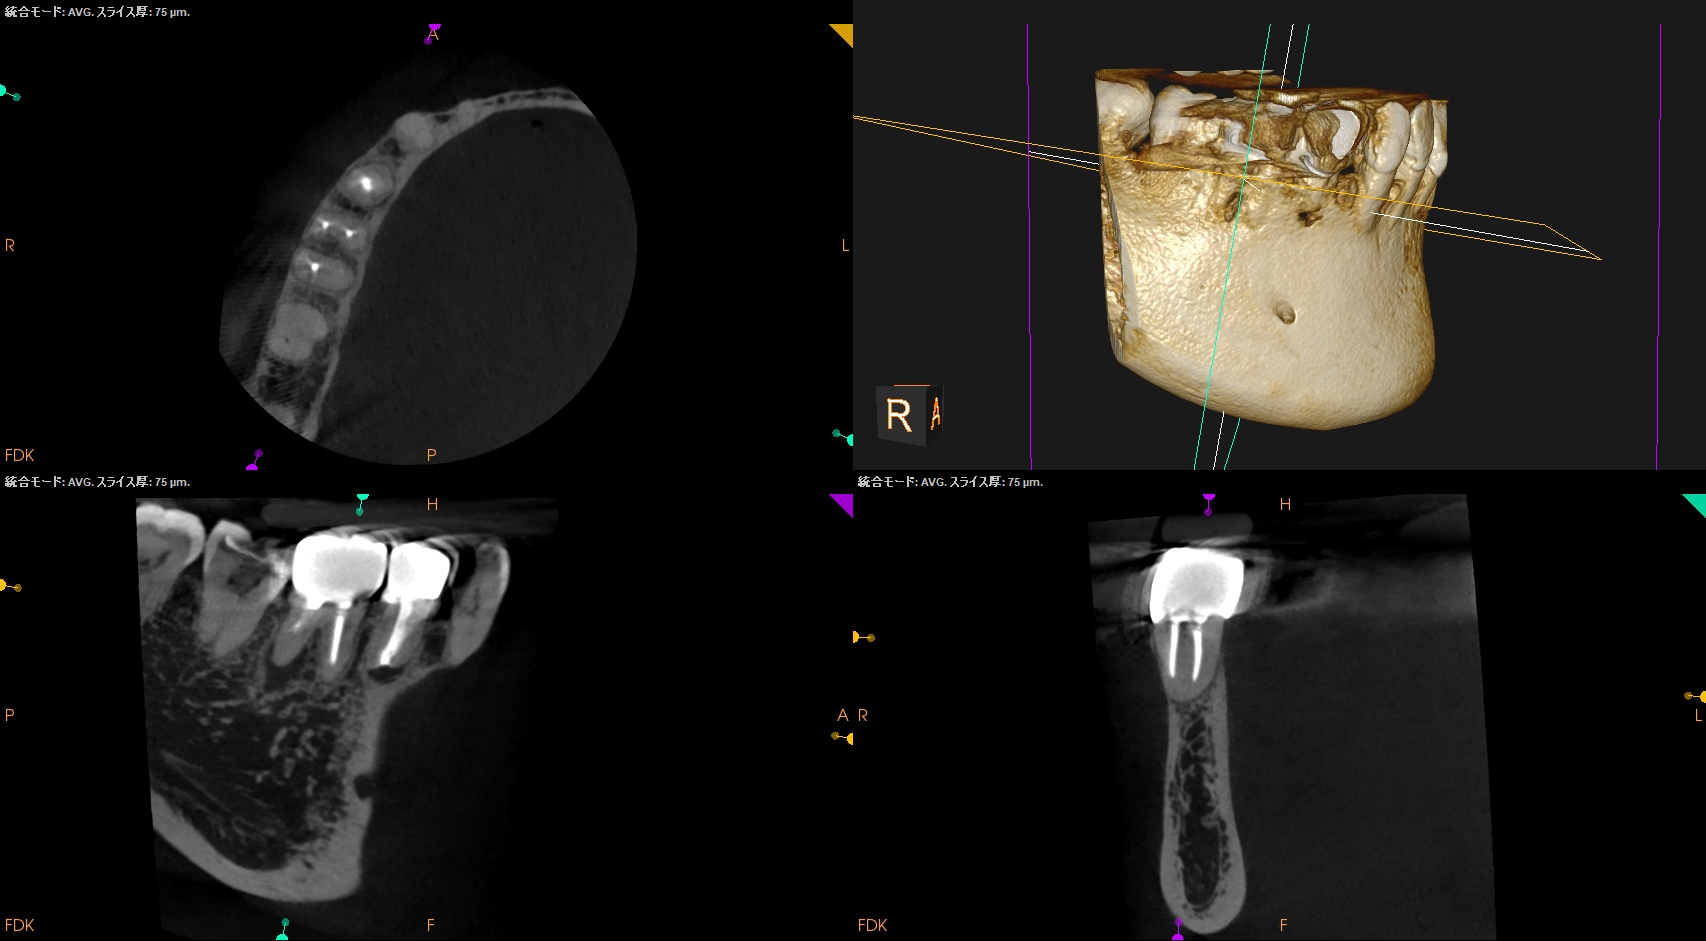

#30 D Apicoectomy(2025.10.8)

OsteotomyしてRoot resectionした。

Retroprepした。ここが一番時間がかかる。

逆根管充填した。

PA, CBCTを撮影した。

問題はないだろう。